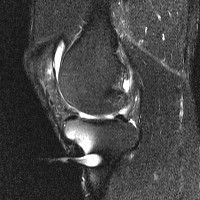

무릎 mri 간단히 봐주실 수 있으시나요 ㅠㅠ

안녕하세요 8년전 십자인대 수술하고 최근 무리한 운동에 무릎 불편감이 생겨서

mri 찍었습니다.

진단결과는 첫 찍은 병원에서 활액막염 이라는 진단을 받았습니다. 혹시 봐주실 수 있으실까요?

진단결과가 달라 혼란스럽습니다 ㅠㅠ

• 안녕하세요. 강성주 의사입니다.

올라온 MRI가 단편적이라서 정확한 진단에 어려움이 있지만 십자인대에는 큰 이상이 있지는 않은것 같으며, 무릎관절내 물이 있는 것으로 보아 활액막염의 진단이 맞을 것 같습니다.

하지만 단편적인 영상이기 때문에 촬영병원에서 정확한 판독지 등을 받으시는 것이 좋겠습니다.